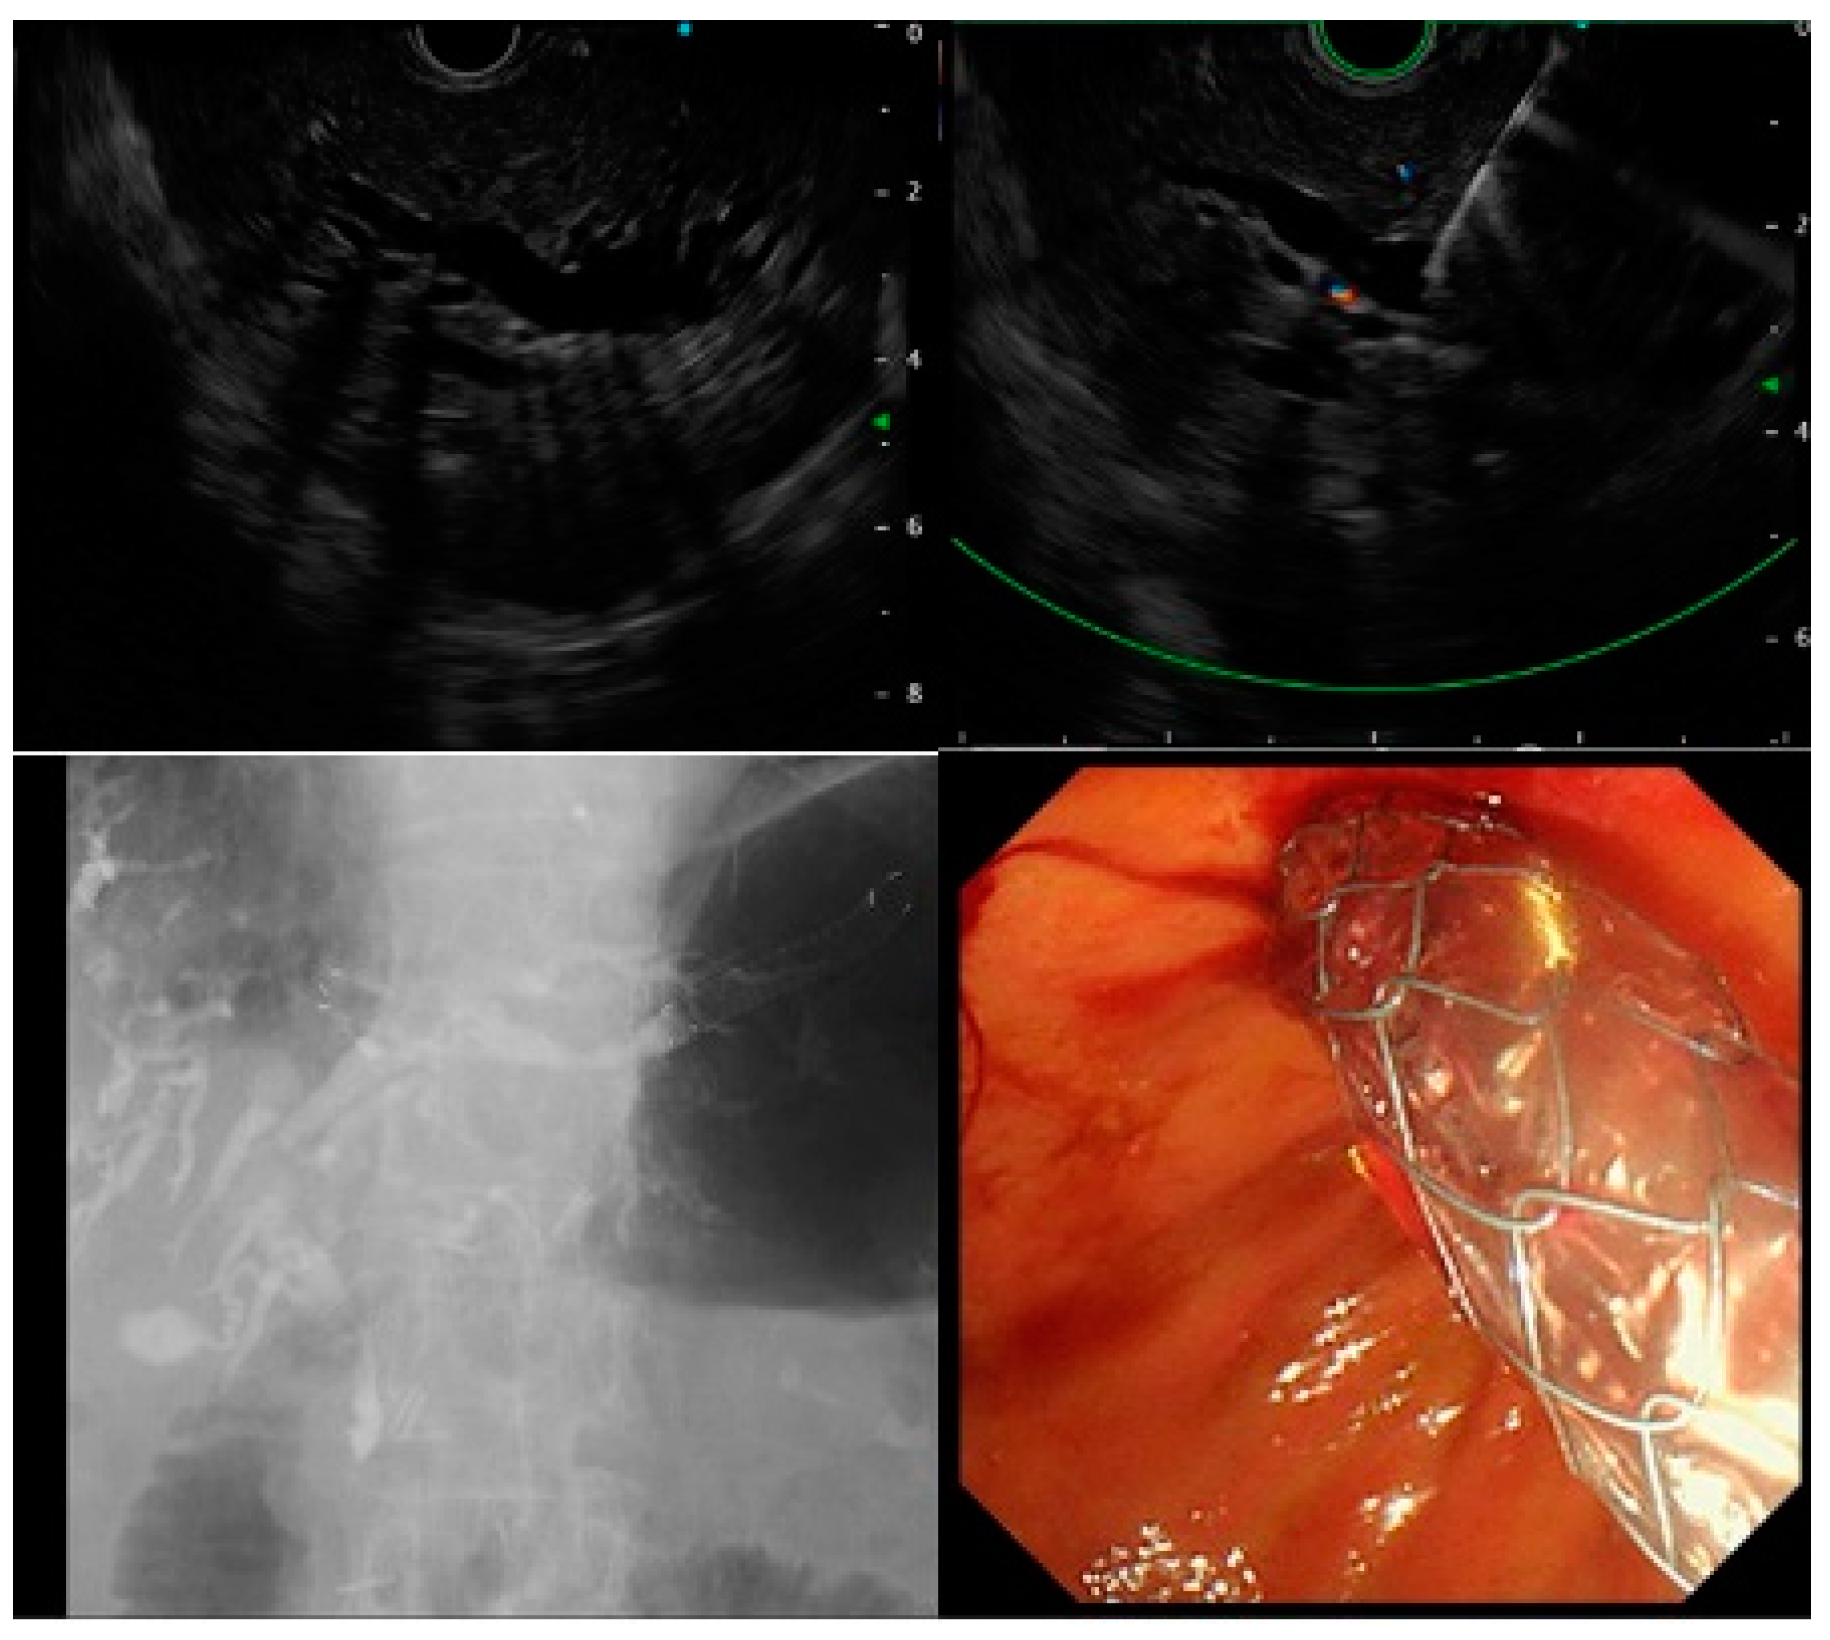

For the EUS-HGS procedure, the intrahepatic bile ducts (B2 or B3) were visualized from the stomach using linear endoscopic ultrasound (GF-UCT260; Olympus Medical Ja-pan, Tokyo, Japan). The intrahepatic bile duct was punctured with a 19-G or 22-G puncture needle, and a guidewire was placed. After cholangiography, fistula dilation was performed using a dilation device, and the PS or SEMS was deployed. Alternatively, the PS or SEMS was placed without dilating the fistula (Figure 2).

Figure 2.

Procedure of endoscopic ultrasound-guided hepaticogastrostomy.